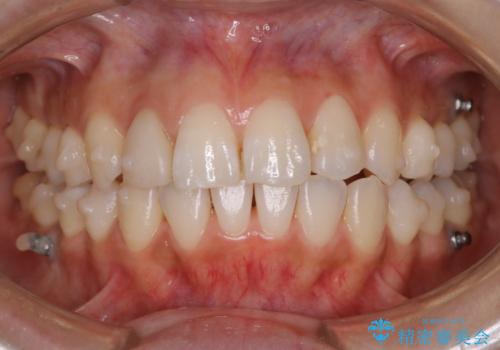

インビザラインの矯正中の方でアタッチメントが歯に付いているため、2ヶ月で着色やプラークが付いてきてしまいました。ホームケアや飲食の仕方により個人差はありますが、基本的には汚れが普段よりもつきやすいです。

定期的にクリーニングすることをおすすめします。